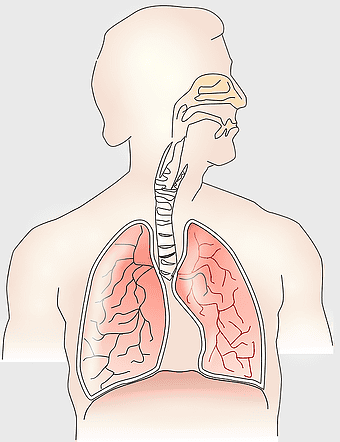

Pulmonary edema symptoms, chronic obstructive pulmonary disease diagram, kidney failure effects on lungs, pulmonary circulation illustration, lung disease diagnostic, respiratory health visuals, human anatomy respiratory system, PNG

- pulmonary edema symptoms

- chronic obstructive pulmonary disease diagram

- kidney failure effects on lungs

- pulmonary circulation illustration

- lung disease diagnostic

- respiratory health visuals

- human anatomy respiratory system